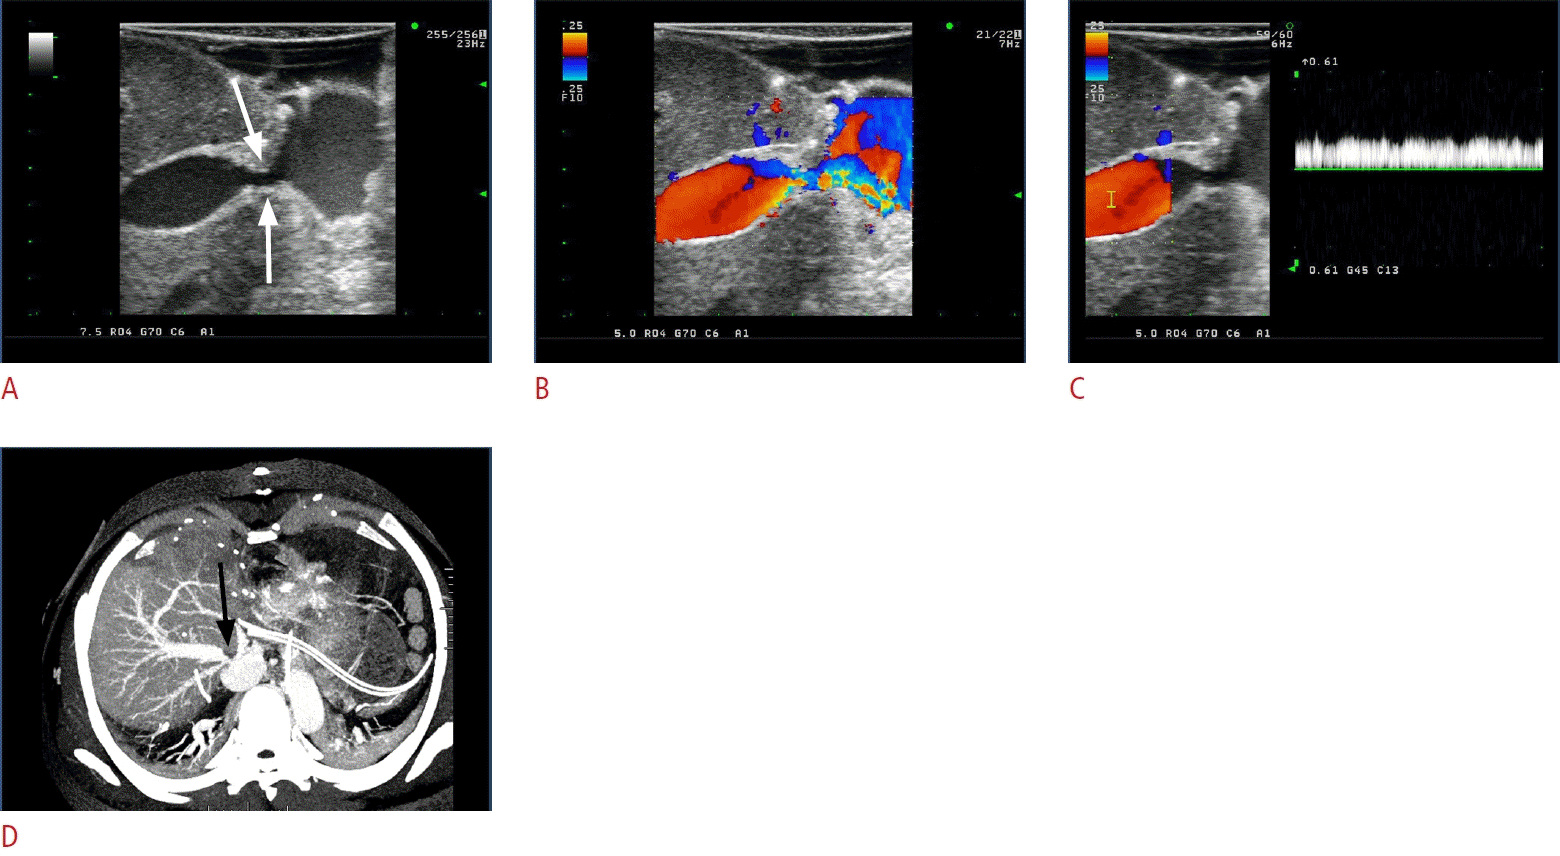

Fig. 1.

Normal grayscale intraoperative ultrasonograms of hepatic artery.

Intraoperative ultrasonogram (A) shows short linear echoes encircling the lumen (arrowheads), suggesting reverberation echo from each of anastomotic stitches. The color Doppler (B) and spectral (C) ultrasonograms show normal color flow and spectral pattern of graft hepatic artery. GHA, graft hepatic artery; RHA, right hepatic artery.

It has been shown that high-frequency (8-12-MHz) IOS, with superb resolution visualizing reverberation echo from each of anastomotic stitches, is capable of assessing the HA anastomosis as it is [3] (Fig. 1). There may be a technical difficulty in case of vascular tortuosity and small size of the vessels.